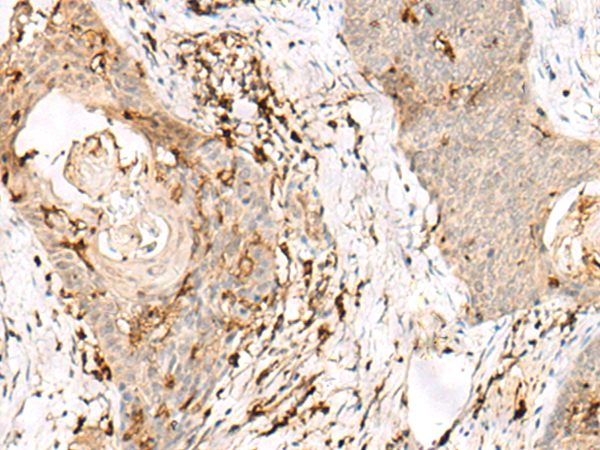

分类: 科研抗体货号: P09880别名: PDIR应用: WB,IHC反应种属: Human, Mouse, Rat

分类: 科研抗体货号: P09886别名: CHED; CHED1; CHED2; PPCD1; ZNF339; EUROIMAGE566589应用: WB,IHC反应种属: Human, Mouse

分类: 科研抗体货号: P09879别名: IDDM1; CELIAC1; HLA-DQB应用: IHC反应种属: Human

分类: 科研抗体货号: P09884别名: DR4; DRB4; HLA-DR4B应用: WB,IHC反应种属: Human

分类: 科研抗体货号: P09883别名: SS1; DRB1; HLA-DRB; HLA-DR1B应用: WB,IHC反应种属: Human